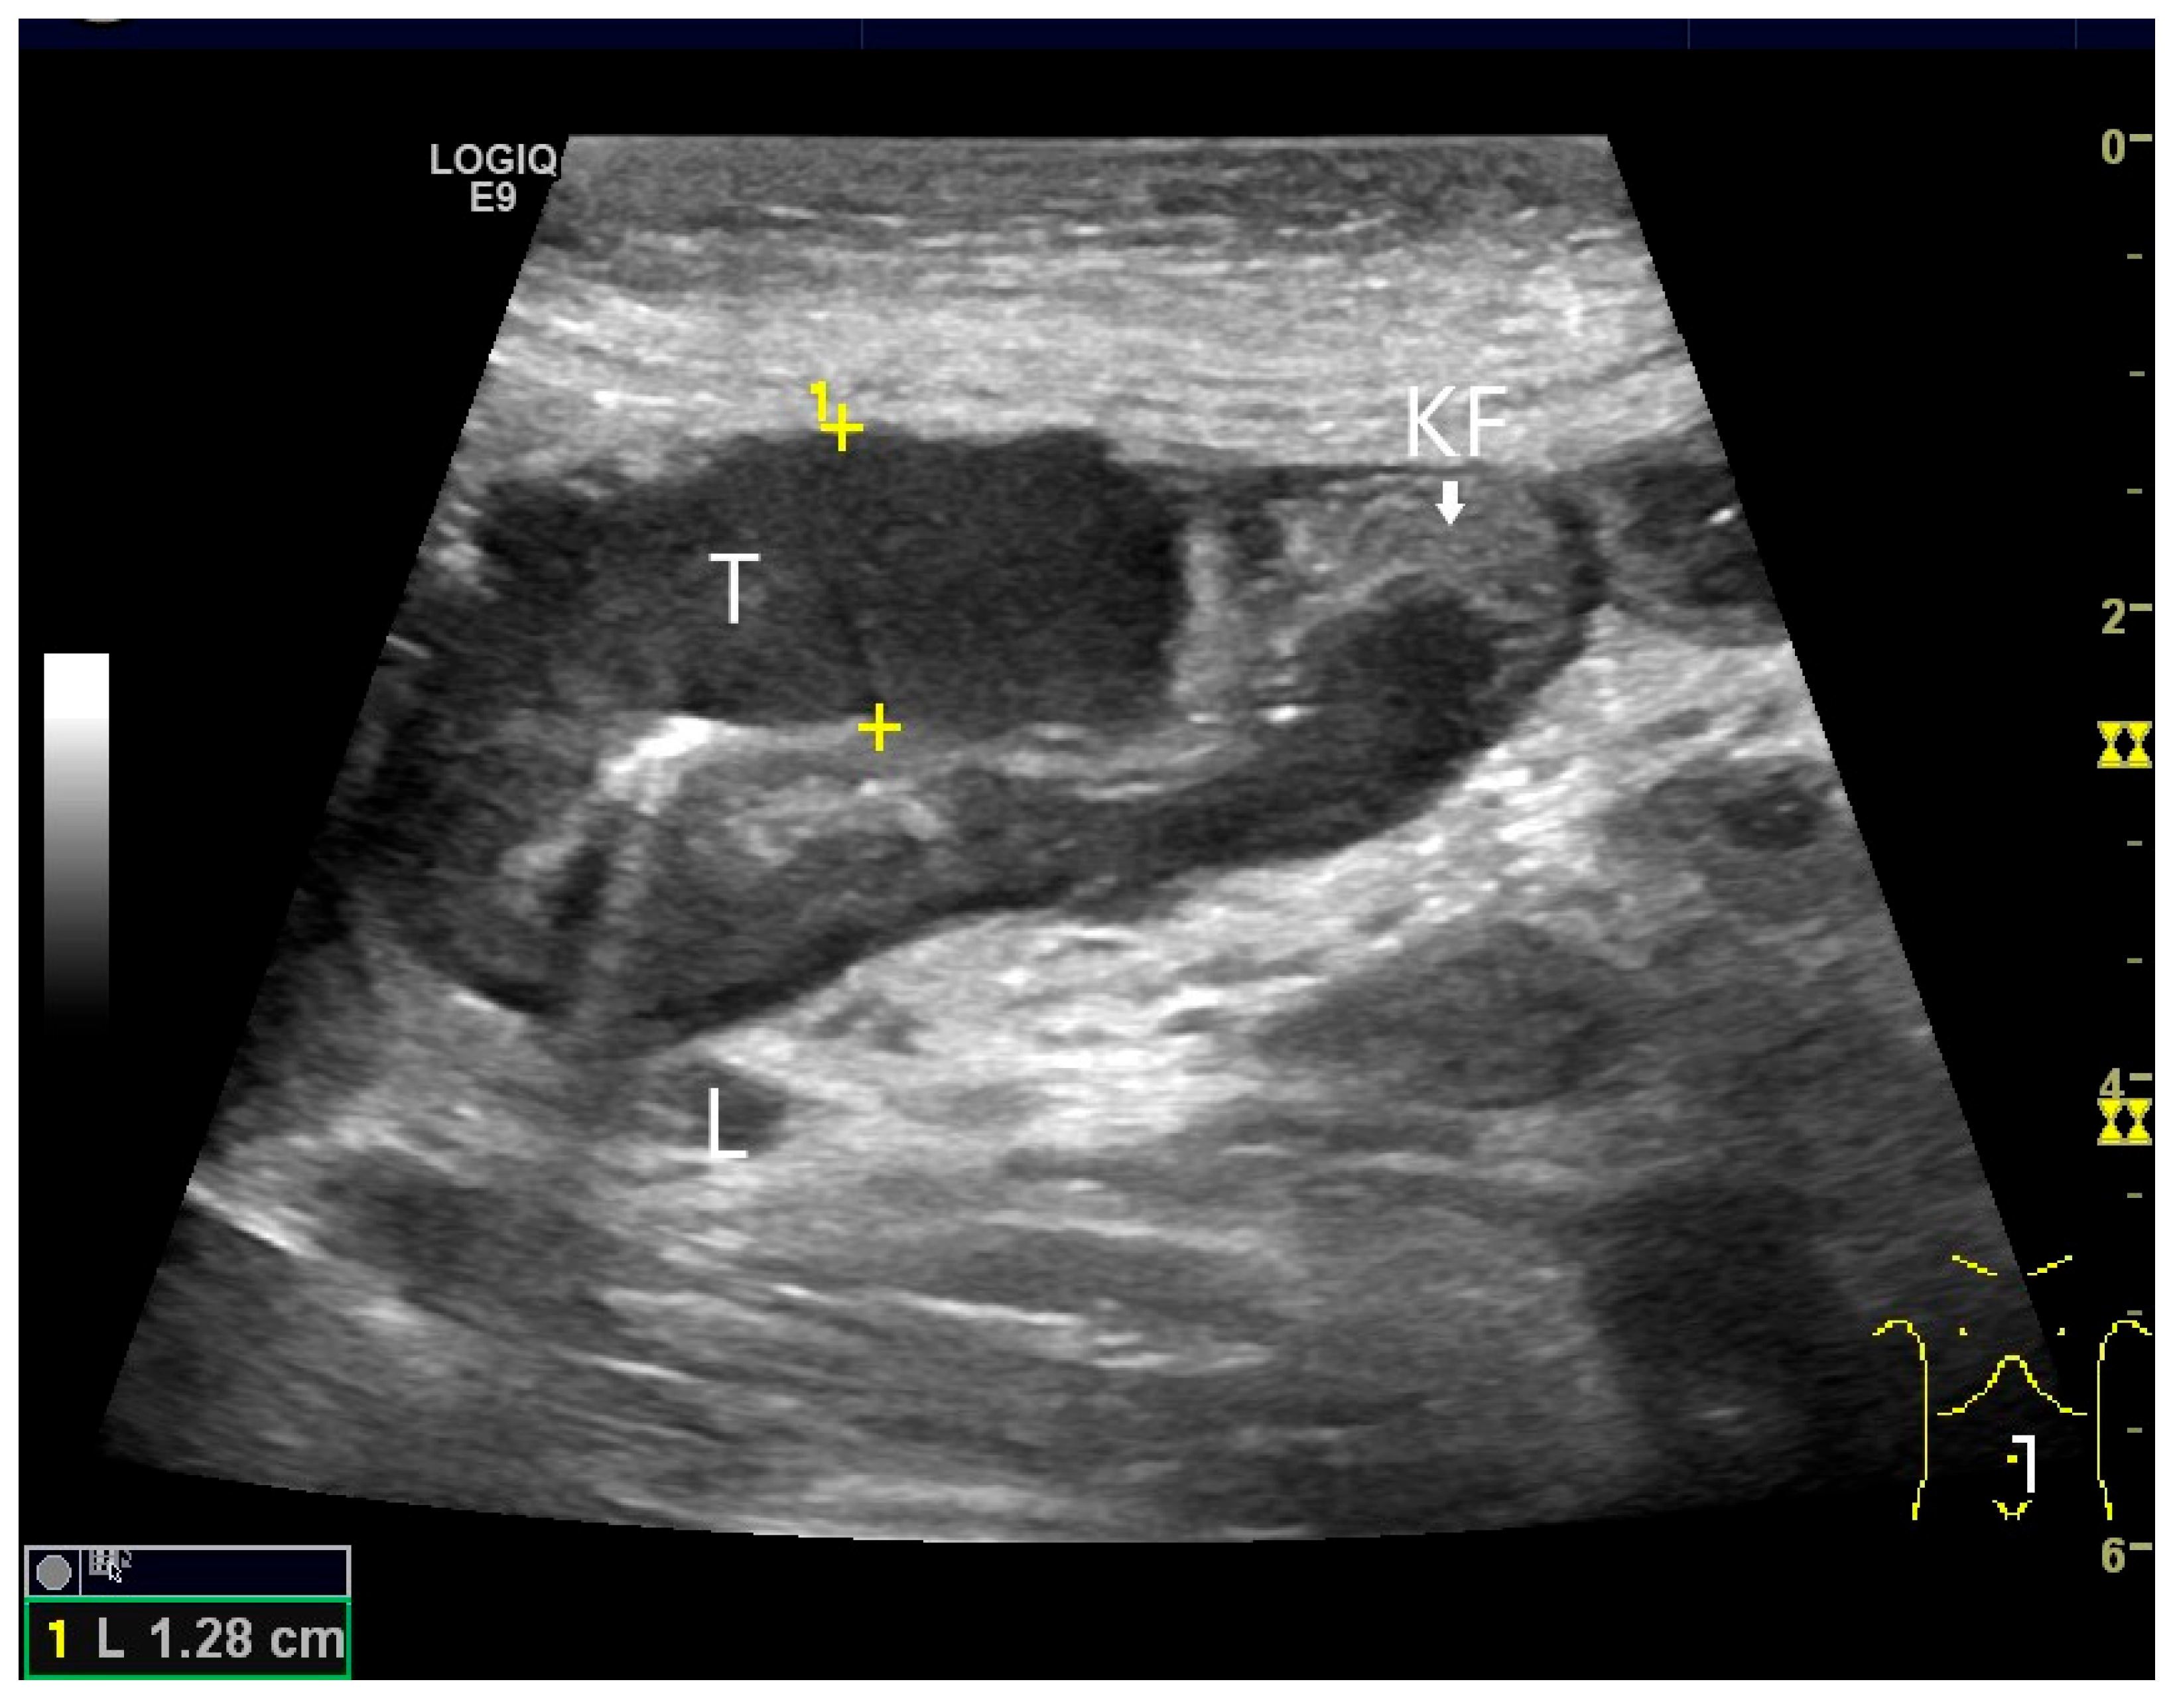

Ultrasound Imaging of Small Intestine NEN

- Schwarze, V.; Marschner, C.; Grosu, S.; Rübenthaler, J.; Knösel, T.; Clevert, D.A. Modern sonographic imaging of abdominal neuroendocrine tumors. Radiologe 2019, 59, 1002–1009. [Google Scholar] [CrossRef] [PubMed]

- Smereczyński, A.; Starzyńska, T.; Kołaczyk, K. Mesenteric changes in an ultrasound examination can facilitate the diagnosis of neuroendocrine tumors of the small intestine. J. Ultrason. 2015, 15, 274–282. [Google Scholar] [CrossRef]

| Neuroendocrine tumor | Small, nodular hypoechoic wall thickenings, mostly in the submucosa with spreading into the other layers. Usually with small vessels on CDI. Regionally enlarged lymph nodes. Multilocular manifestations are possible. |